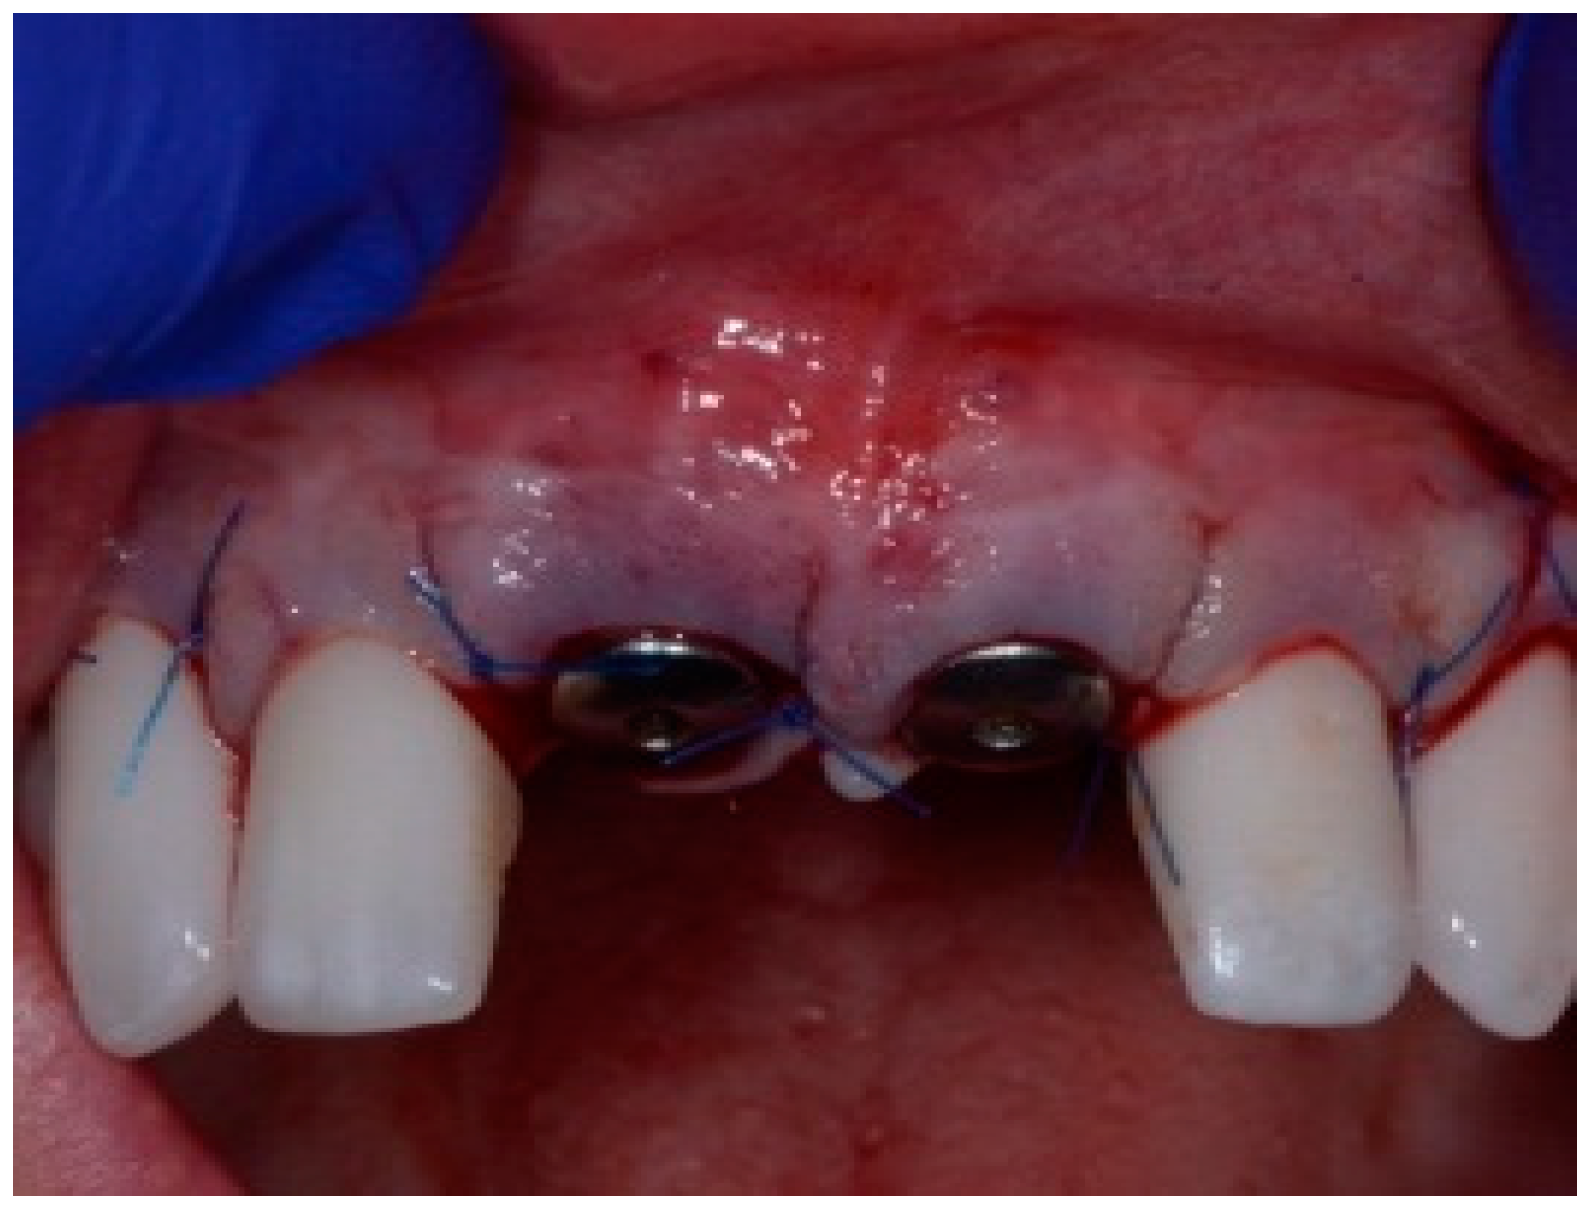

Before the graft and membrane is placed over the defect, a periosteal dissection must be performed to release flap tension to facilitate its coronal advancement and closure. The horizontal incision is made 1 mm deep into the periosteum, apical to the mucogingival junction, in a single plane along the length of the flap, connecting the two vertical releasing incisions. After the placement of this shallow incision, a micro-elevator is used to stretch within the incision line. This stretching not only releases the tension within the flap but also allows a more coronal advancement of the flap margin for eventual primary closure, minimizing postoperative incision line opening. This important step in flap management is performed before the placement of the graft material because the periosteal-releasing incision is associated with increased bleeding, which will complicate the graft, the membrane placement, and stabilization. A composite graft material consisting of allograft and xenograft in a 50/50 mix was placed in the gap between the implant and the socket wall over-contouring the facial wall defect (Figure 4). Two healing abutments were placed on the implants, followed by a bioabsorbable collagen membrane (Zmatrix, Osteogenics, Lubbock, TX 79424, USA) placed over the surgical area, which was closed with 5.0 polypropylene sutures (Figure 5). An Essex appliance, fabricated inhouse using a standard suck-down process, was inserted postsurgically. The implants were allowed to heal in a non-submerged environment for a period of 6 months.

Figure 5.

Clinical view of the final flap closure.